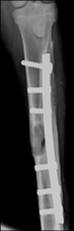

0�� 3���� 12W�� 24W�� 44W